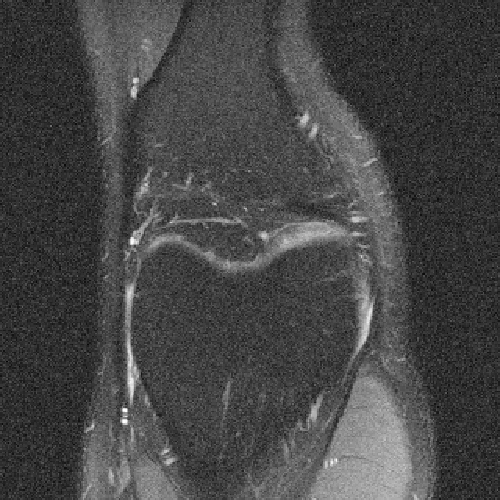

To illustrate this fact, we conducted a simple experiment in Fig. 1. Starting from two similar initial sampling trajectories, we let a multi-scale solver run for 14 epochs and 85 hours on the fastMRI knee database. We then evaluate the average reconstruction peak signal-to-noise ratio (PSNR) on the validation set. As can be seen, the final point configuration and the average performance varies by dB, which is significant. This suggests that the algorithm was trapped in a spurious local minimizer and illustrates the difficulty to globalize the convergence.

dB